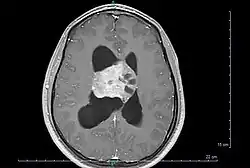

Axial T1-weighted gadolinium-enhanced MRI image showing an enhancing mass with cystic changes consistent with central neurocytoma in the right lateral ventricle. | |